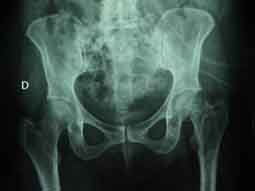

Figure 5

. Standard graphic view of pathological fracture of the left neck of femur.